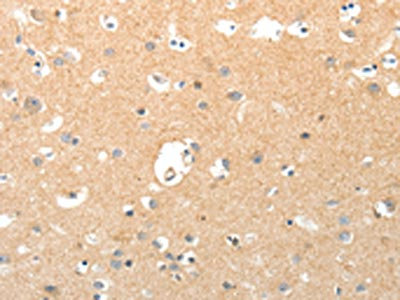

The image on the left is immunohistochemistry of paraffin-embedded Human brain tissue using CSB-PA976408(TNXB Antibody) at dilution 1/40, on the right is treated with synthetic peptide. (Original magnification: ×200)